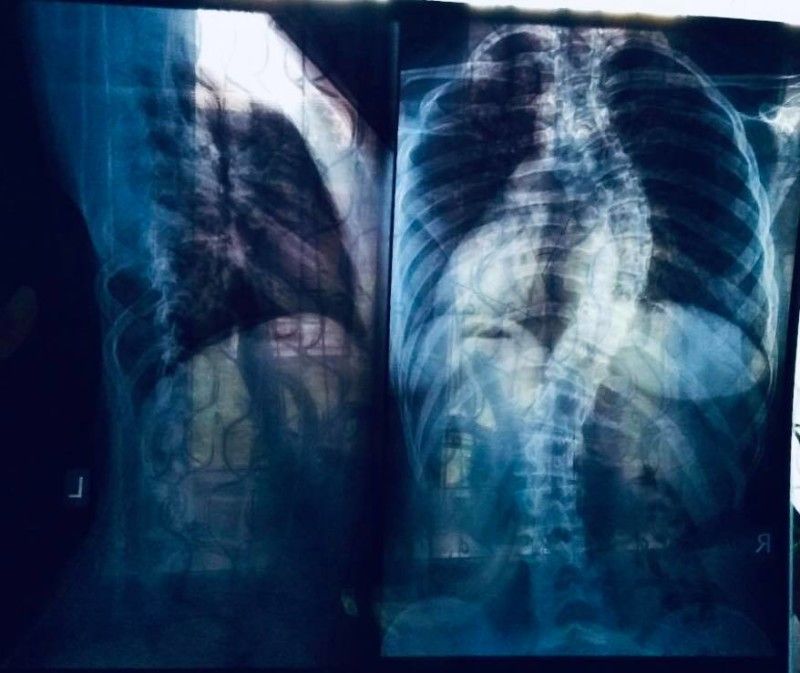

Альона Захарчук, жителька села Тур має IV ступінь сколіозу і потребує дороговартісної операції

ГО "Молодь Ратнівщини" організовує за підтримки Ратнівської районної державної адміністрації ярмарку солодощів для збору коштів Альоні Захарчук, жительки села ТУР. Дівчина навчається в 11 класі і має IV ступінь сколіозу. Домогти дівчині погодилися в ОХМАДИТі. Операцію проведуть безкоштовно, але імплантанти коштують 150 тисяч гривень.Таких грошей у родини немає.Тато помер три роки тому, залишивши дружину із двома дітьми.

Як повідомляла у Фейсбуці відома волонтерка Наталія Попова, у дівчинки підліткова аномалія: швидко викривився хребет і треба терміново вживляти імпланти, вартістю 150 000 грн... Завдяки небайдужим, вже зібрано 77% від необхідної суми – 115 000 гривень. Допомогти може кожен: